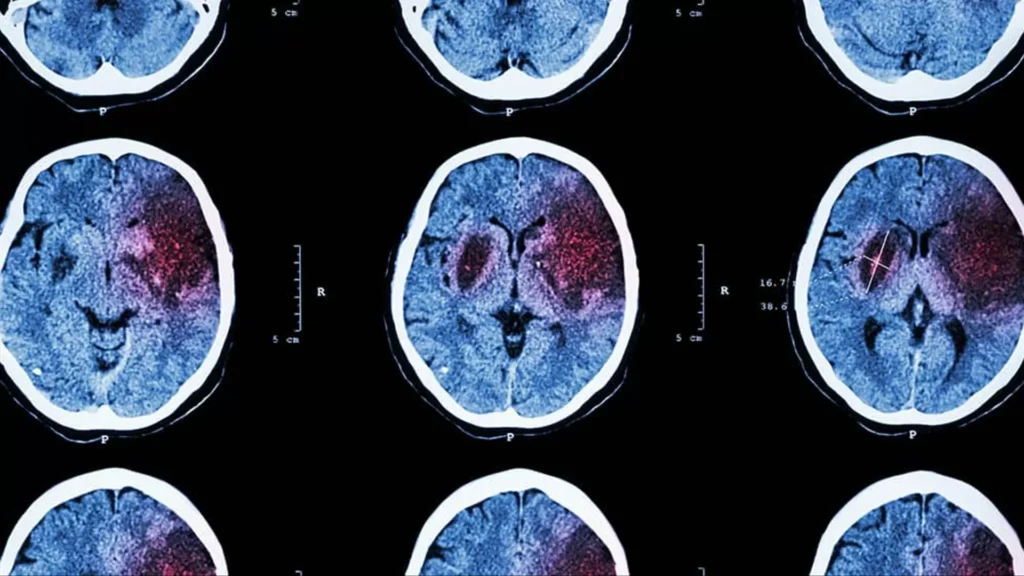

Os pesquisadores utilizaram técnicas de neuroimagem para monitorar a atividade cerebral de voluntários enquanto eles realizavam tarefas que envolviam tomada de decisão. Eles descobriram que, além do córtex pré-frontal, outras regiões do cérebro, como o córtex parietal e o córtex cingulado anterior, também estavam ativas durante o processo de tomada de decisão.

Mas o que é ainda mais surpreendente é que essas áreas não trabalham de forma isolada, mas sim em conjunto, em uma espécie de “rede de tomada de decisão”. Os pesquisadores observaram que essas regiões se comunicam entre si por meio de sinais elétricos e químicos, coordenando suas atividades para chegar a uma decisão final.